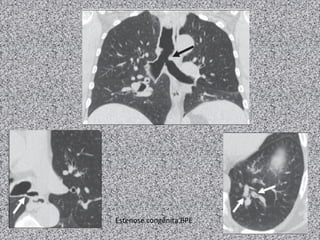

Bronquiectasia focal

Estenose congênita BPE